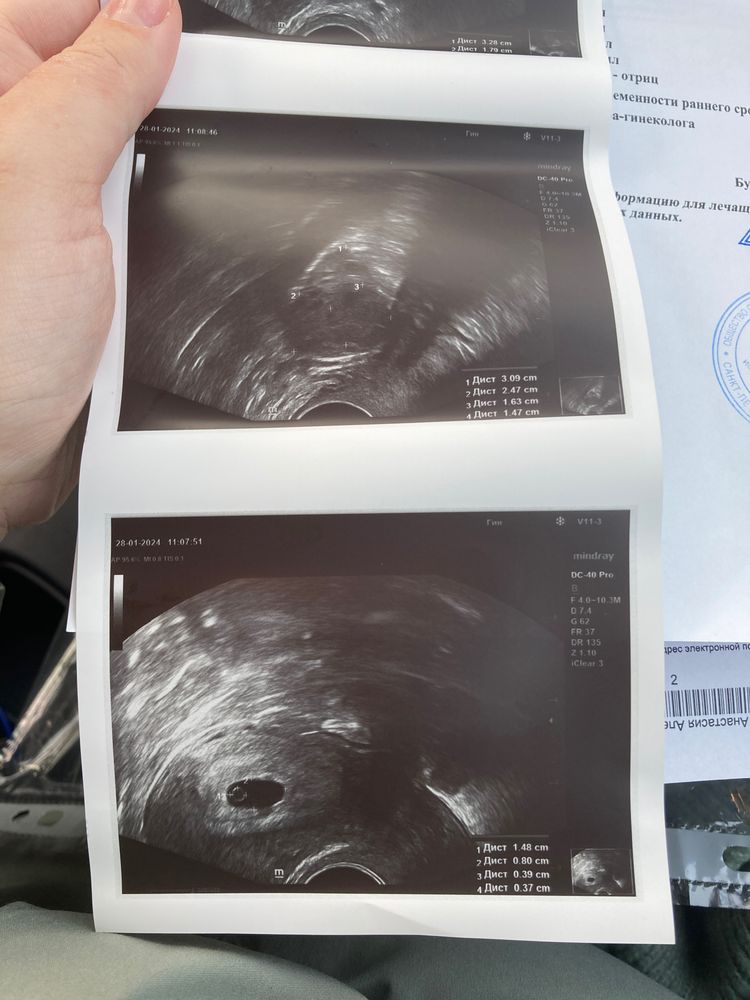

Сходила на узи, врач сказала, что то, что видно - слишком маленькое для срока и ничего не ясно. Посмотрите, пожалуйста, заключение. Срок 6+0

КТР 3,9 мм (0,39 см) соответствует акушерскому сроку (по месячным) 6 недель, нормально у вас все (в заключении похоже эмбриональный срок, он ровно на 2 недели меньше акушерского)

Ваш ктр это 6 недель . Обычно можно увидеть уже сб , но узисты и аппараты разные . Должны были сильнее приблизить и посмотреть пульсацию .по идее эмбрион размером с жм должен быть, но на этом снимке почему то его не видно

Кажется, жм и эмбрион у меня на разных снимках, 4 и 1 соответственно. Врач много говорила про несоответствие срокам, я перепугалась и даже не подумала попросить посмотреть сб тщательнее…

Ктр у вас по сроку,3,9 мм это 6 недель акушерских, единственное что сб нет,но может аппарат не очень,в заключении не акушерский срок